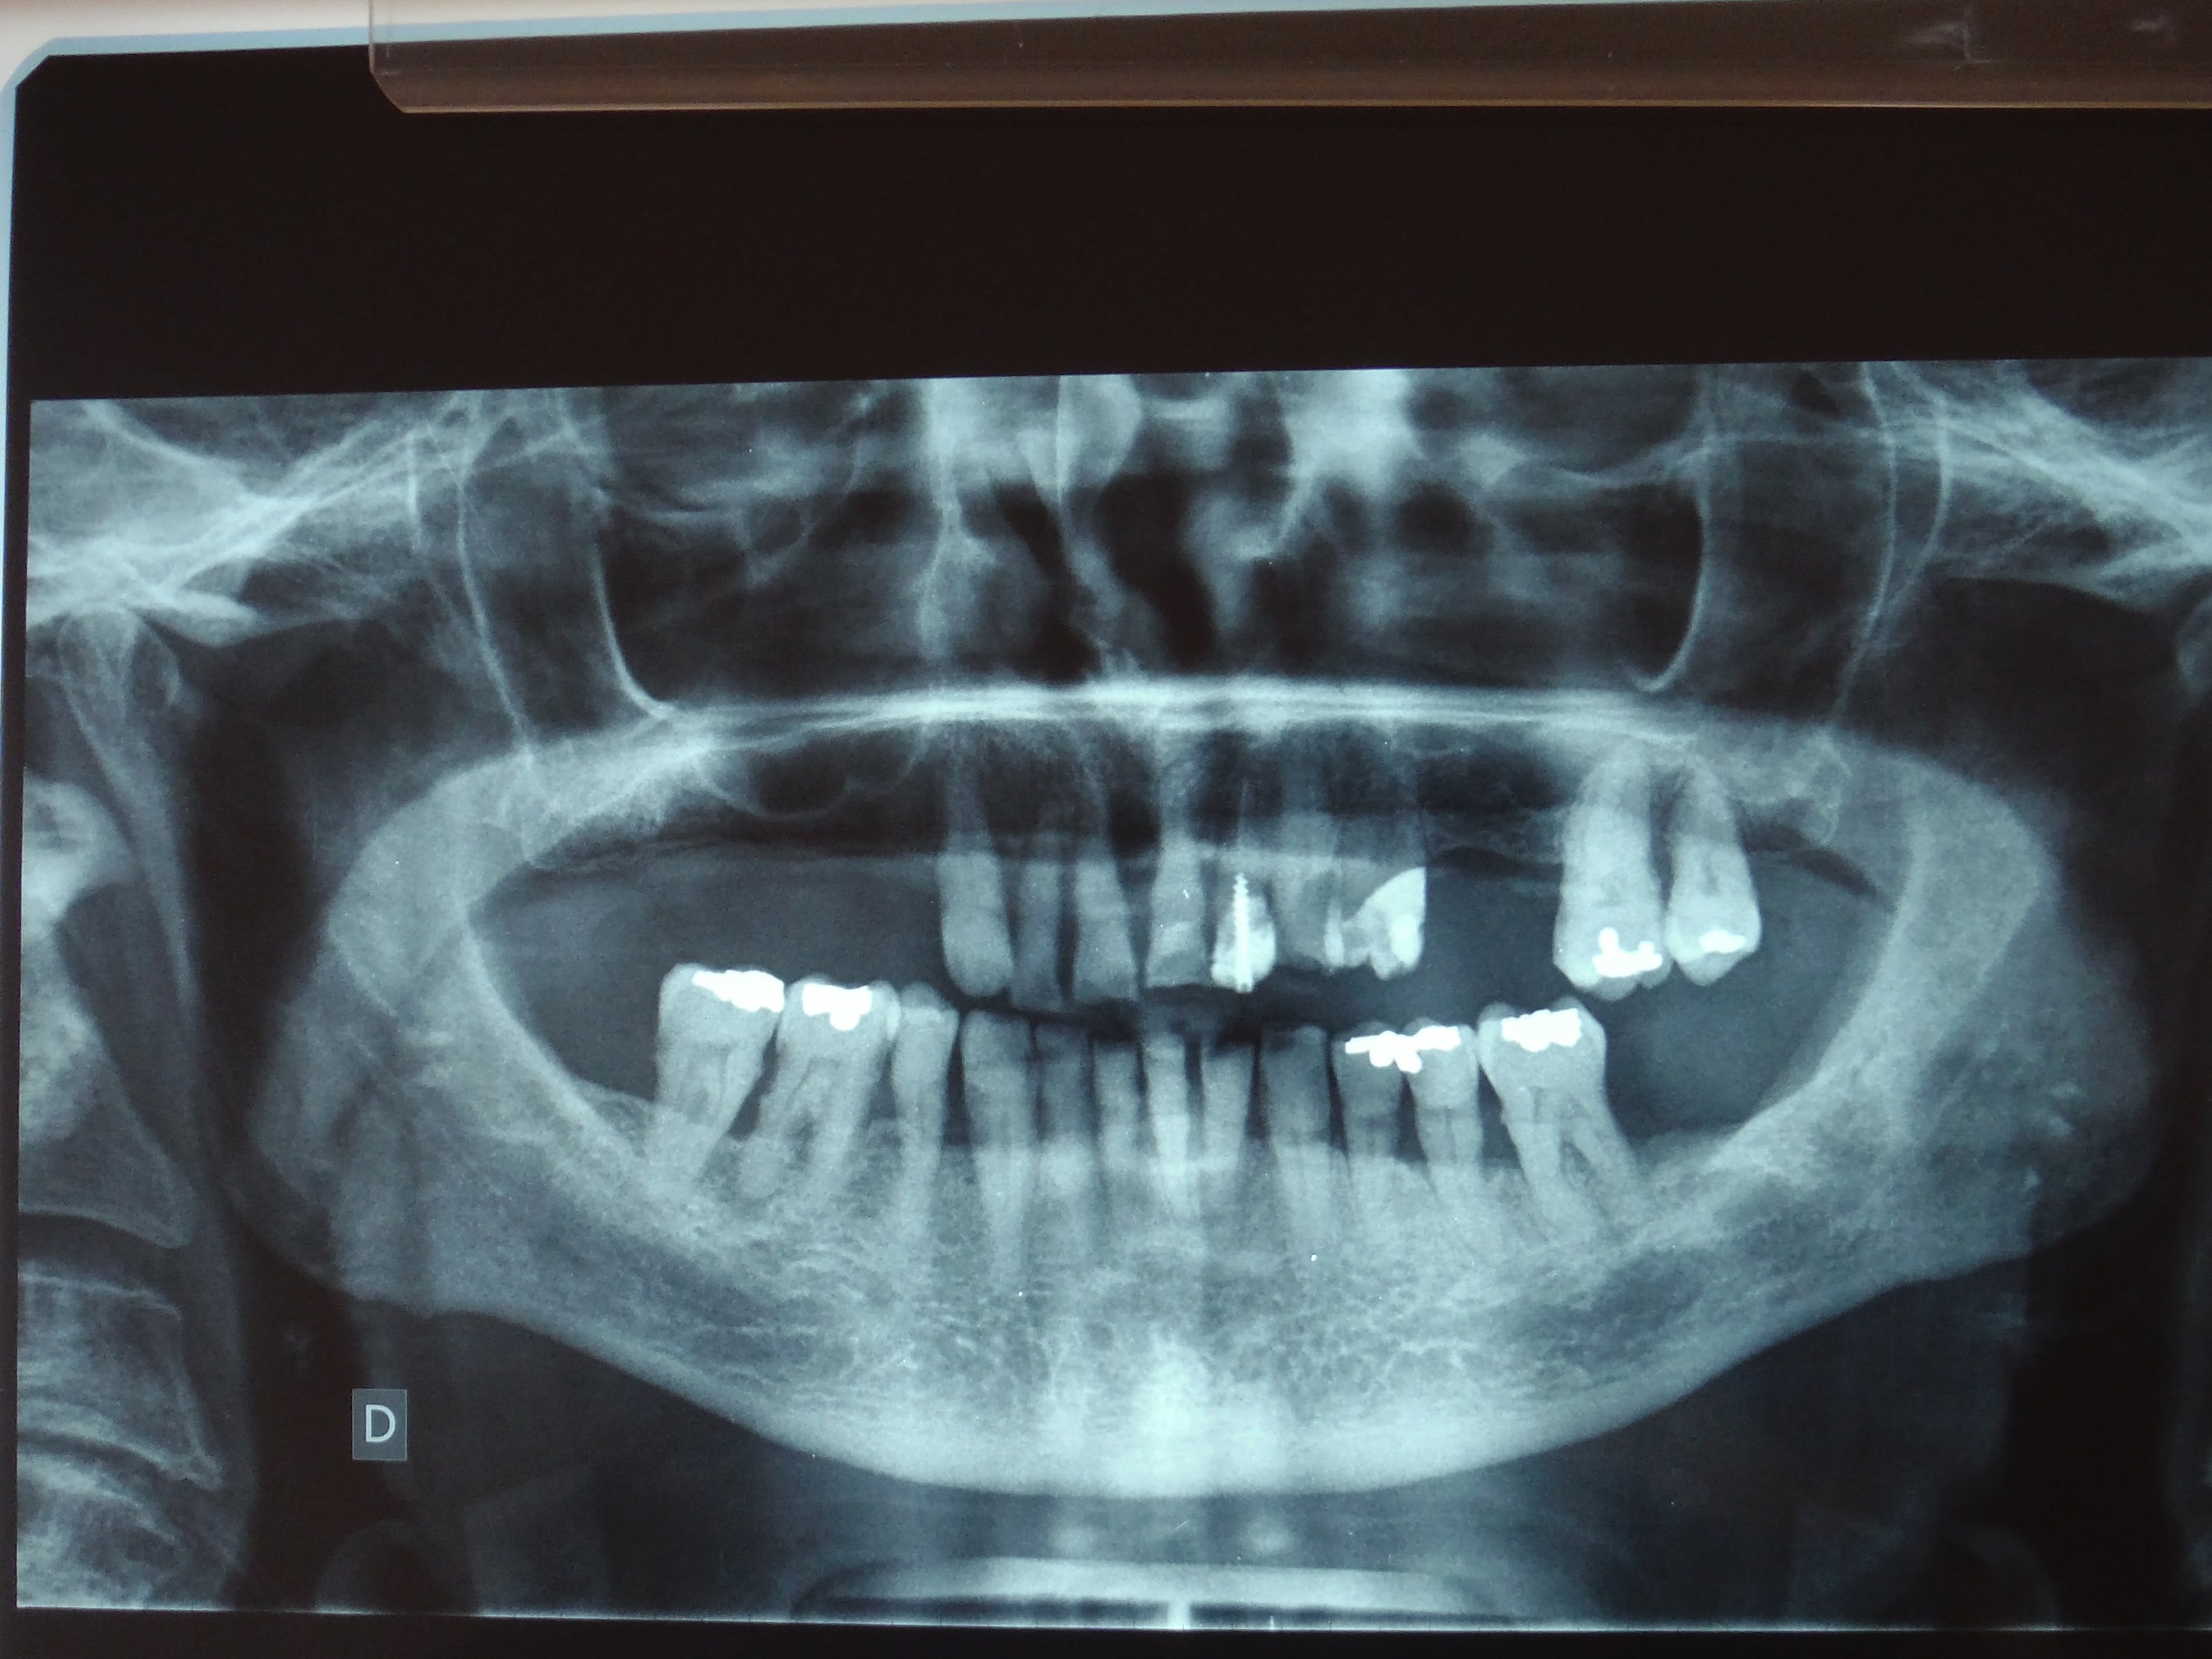

je l'ai trouvé.

Et qu'est-ce qu'il souhaite le patient ?

On voit pas trop sur la pano mais y a plusieurs dents qui ne sont tenues que par quelques mm d'os.

1) surfaçage , les dents mandibulaires sont conservables

2) la réalisation d'une PPA provisoire maxillaire va solliciter encore plus des dents qui ne tiennent pas des masses. Ça ne sera que du bricolage. Et en plus le patient aura eu l'impression d'avoir payé une PPA pour rien puisque toutes ses dents vont bouger et dégager une par une

3) dans ce cas ça me choquerait pas qu'un praticien dise pour le maxillaire

- extraction , complet immédiat

-OU BIEN extraction, implantation immediate et mise en charge immédiate ou précoce SI c'est possible , après annalyse du scanner et l'analyse pré-implantaire

Il vient pour de l'adjointe ;-)

Les 7, PM et C sont exploitables, il n'a jamais été appareillé (et c'est important!), une partielle est préférable, quitte à ce qu'elle soit évolutive.

La pano est moche, très vieux cas, qu'aurais tu fait?

On vire tout le maxillaire, et tout ce qui est postérieur aux 4 à la mandibule. Des crochets sur des 5 mandibulaires qui ont subi un traumatisme occlusal, ça me plaît pas trop. Donc je vire les 5 également.

Complet immédiat, PPA provisoire mandibulaire

Ou encore une solution implantaire au maxillaire , voir même à la mandibule. Après assainissement paro réévaluation et Rdv de maintenance